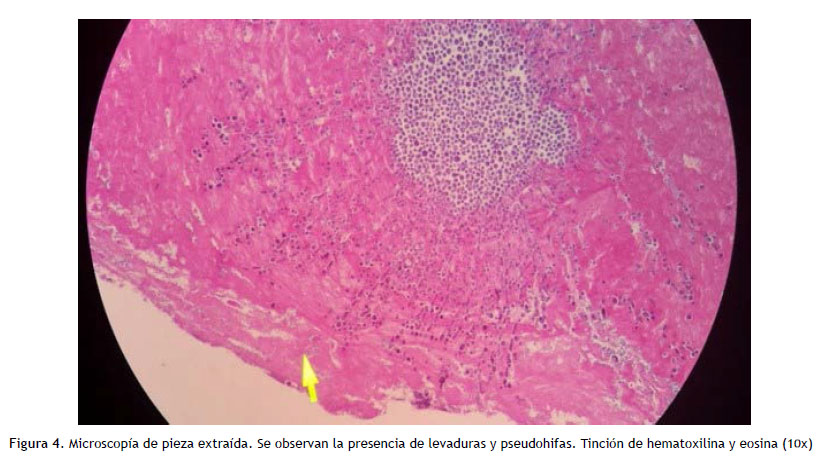

Inició cobertura empírica para endocarditis con imipenem y vancomicina, con resultados de hemocultivos periféricos negativos. No se tomaron muestras de la punta ni del septum subcutáneo. Por la sospecha de endocarditis fúngica, se decide retiro del dispositivo intravascular mediante toracotomía, siendo realizado a las 48 horas del inicio de antibióticos, objetivándose la presencia de importante biofilm (Figura 3), con resultado de cultivo directo de la pieza extraída que reportaba C. parapsilosis (Figura 4). La susceptibilidad de la cepa fue la misma que el episodio previo de candidemia y se dirigió la cobertura antifúngica con caspofungina 70mg EV dosis de carga y luego completó 30 días con 50mg EV/día, posterior al retiro del PAC y negativización de hemocultivos, continuando con fluconazol 800 mg/día por 2 semanas adicionales.